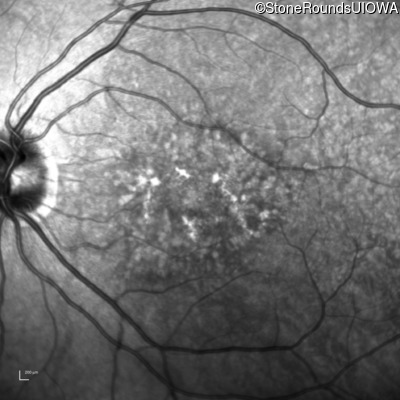

Infrared Fundus Photograph - Left - 20/25 +2 sc

Exemplar